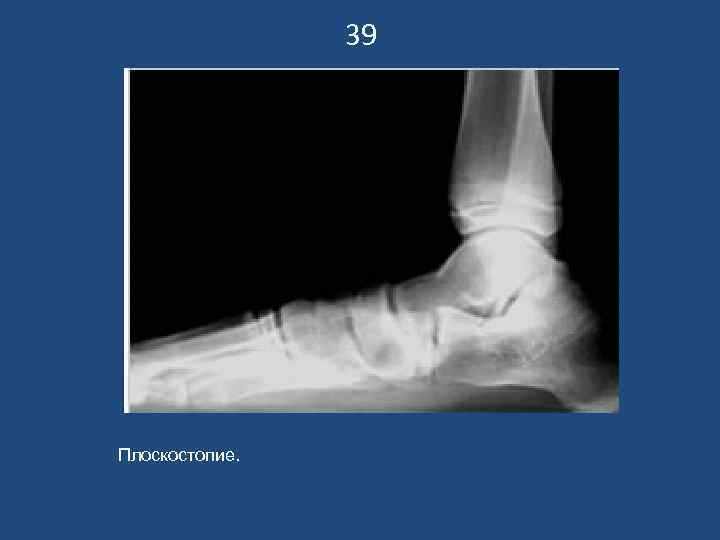

39 Плоскостопие.